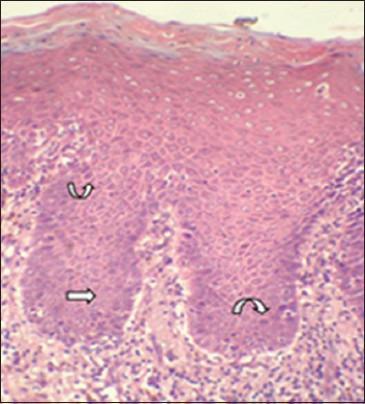

Expression of cyclin D1 in group 3 was significantly higher than in group 1 and 2 (P < 0.001, P = 0.028), expression in group 2 was significantly higher than in group 1 (P = 0.003) and were statistically significant. Generally expression of cyclin D1 was confined to lower one-third of epithelium and was highest in mild dysplasias. Among 13 atypical morphologic features, cyclin D1 expression consistently correlated with basilar hyperplasia.

第3组中细胞周期蛋白D1的表达显著高于第1组和第2组(P < 0.001,P = 0.028),第2组中的表达显著高于第1组(P = 0.003),差异具有统计学意义。一般来说,细胞周期蛋白D1的表达局限于上皮的下三分之一,在轻度发育异常中最高。在13种非典型形态学特征中,细胞周期蛋白D1的表达始终与基底增生相关。